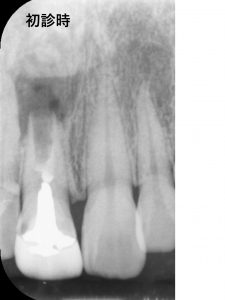

まず初診時のレントゲン所見です。

*印の歯から膿が出ていて

歯がグラグラするとのことで来院されました。

前にかかっていた歯科医院では、抜歯と診断されました。